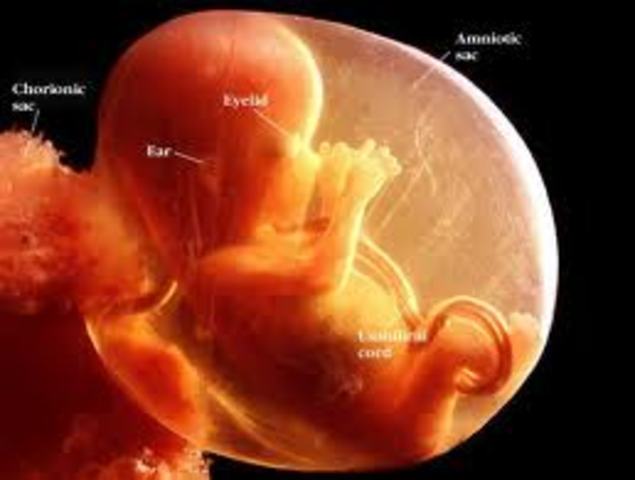

• Week 14

Week 14

The eyelids are fused over the fully developed eyes. The baby can now silently cry, since it has vocal cords. It may even start sucking its thumb. The fingers and toes are growing nails.